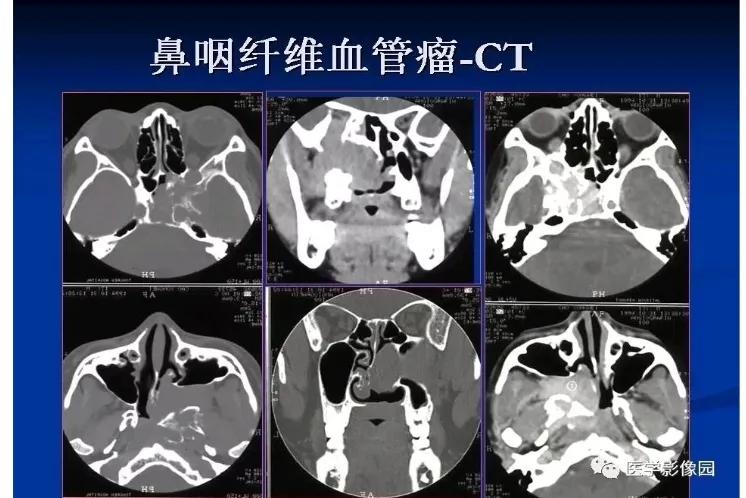

鼻腔、鼻窦及鼻咽部肿瘤:其中最易发生鼻出血者为鼻中隔血管瘤、鼻咽纤维血管瘤、出血性鼻息肉和鼻腔鼻窦恶性肿瘤。少量鼻出血或涕中带血是恶性肿瘤的早期主要症状之一。